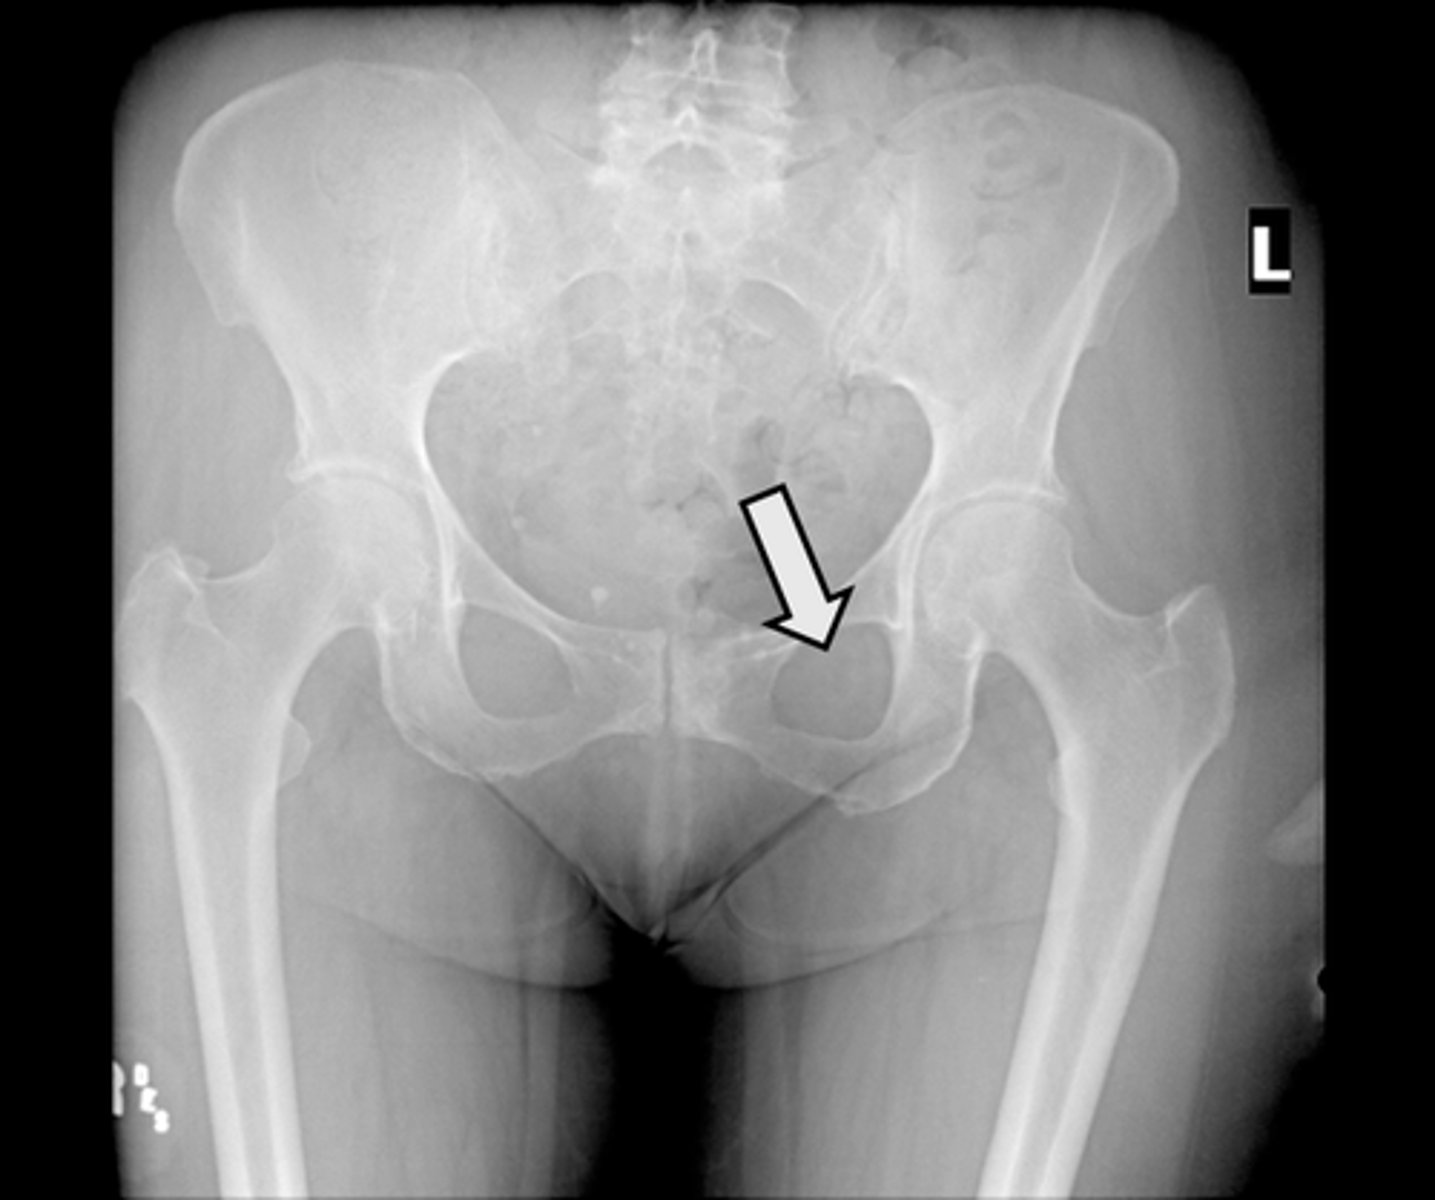

AP pelvis

What is the image?

2

Acetabulum

<p>What is indicated in the image?</p>

New cards

What is indicated in the image?

4

Epiphysial plate

6

Hip joint

8

Ischial spine

10

Nonfused greater trochanter

12

Pubic symphysis

14

Sacrum